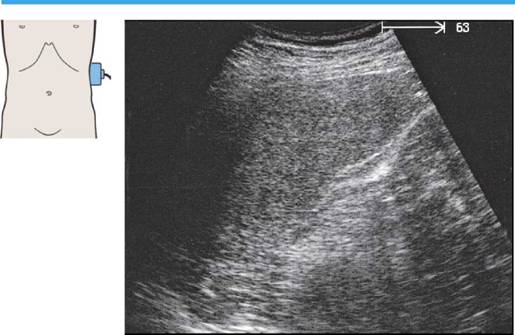

Печень при продольном сканировании

57 Левая доля печени, латеральный сегмент, II и III субсегменты

63 Левая печеночная вена, круглая связка, граница между медиальным и латеральным сегментами, хвостатая доля

По анатомическим критериям в печени выделяют левую и правую доли. Левой доле соответствует латеральный сегмент; правая доля состоит из медиального, переднего и заднего сегментов.

По функциональным критериям латеральный и медиальный сегменты! относятся к левой доле печени, а передний и задний - к правой.

Латеральный сегмент печени состоит из расположенного краниально II субсегмента и расположенного каудально III субсегмента.

Границей между латеральным и медиальными сегментами, т.е. между анатомическими левой и правой долями печени, является левая печеночная вена.